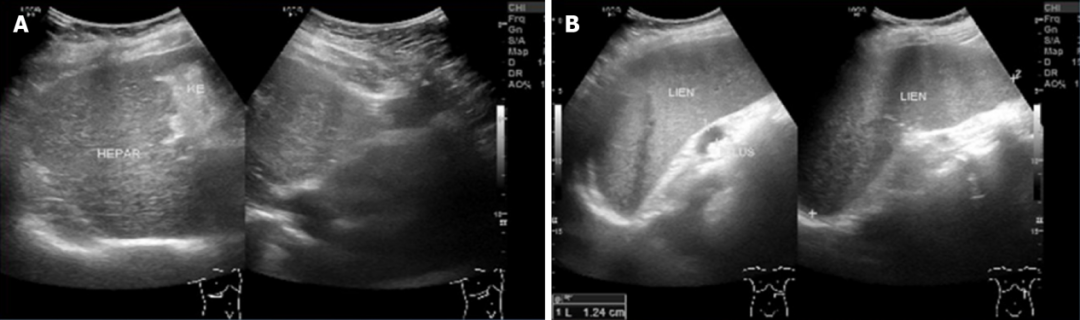

腹部超声检查提示胆囊多发

图1 腹部超声